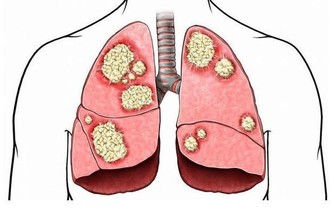

因為有了這一次治療頸椎和胸椎的經驗以後,發現很多患有頸椎病、腰椎病的人,在頸椎以下、腰椎以上相連接的椎體上,均存在著錯位,因此,得出一條重要結論:頸椎有病連著肺,腰椎有病連著胃。

這句話講的是什麼意思呢?頸七椎向下相連的是胸椎的一椎、二椎,這兩個椎體與肺相通,是通往肺的通路,當頸椎扭傷一定牽連到胸椎的一、二椎;腰椎向上相連的是胸十椎、十一椎、十二椎,十一椎、十二椎與脾、胃相通,是通往脾胃的通路,當腰椎扭傷一定牽連到胸十、十一椎。

頸椎下端和腰椎上端的這些部位,往往是在臨床中被遺忘的角落,所以,既影響頸、腰椎的治療,也影響與之相連病症的治療效果。醫者在治療頸椎腰椎的同時,一定要檢查鄰近胸椎椎體的排列狀態,頸椎的治療要注意到肺(胸一、二椎),腰椎的治療要注意到胃(胸十、十一椎),這是治療頸椎腰椎病症的關鍵。